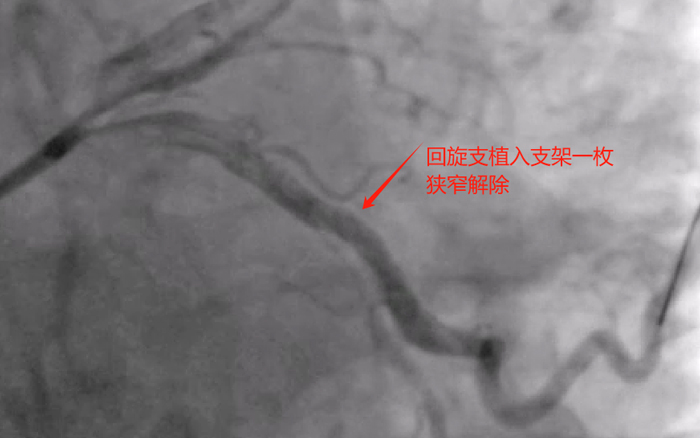

周一下午,再次为老陈进行第二次冠脉介入治疗,术中快速处理左冠前降支及回旋支重度狭窄病变,并植入支架两枚,同期简单处理右冠后三叉至后降支重度狭窄病变,一枚药物球囊处理,中段远段狭窄均无影响,完美结束手术。手术总用时1小时,造影剂用量100ml,手术很顺利,比预想的效果要好,已经超预期完成。